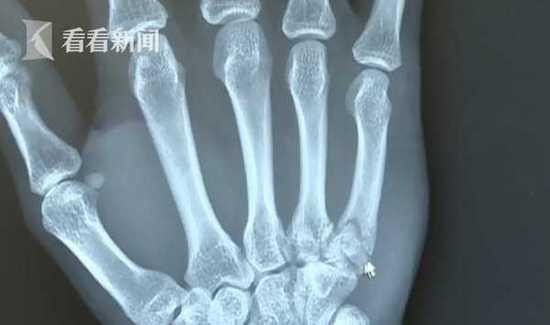

CT显示,小沈的手掌果然是骨折了,而且还很严重,骨头也错位了。医生说,小沈的手最少要一个月才能恢复。这样的患者医生还是头一次遇到,医生提醒球迷,要注意健康。